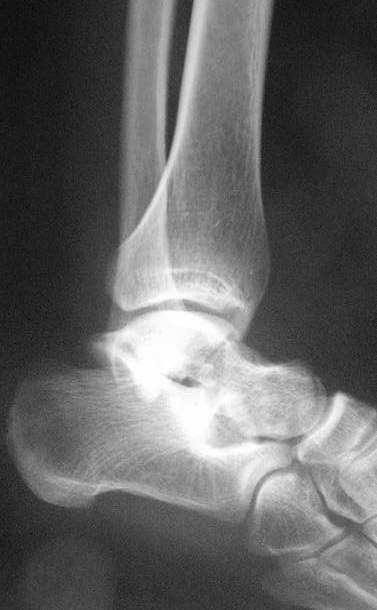

Переломовывих тарана с повреждением медиальной стороны. Через 4 часа после поступления проведена репозиция и фиксация тарана после Irrigation&Debridment. Частичное несращение медиальной лодыжки не беспокоит, вернулся к активному образу жизни. Полная нагрузка разрешена через 11 недель. Финальные снимки через 11 месяцев.